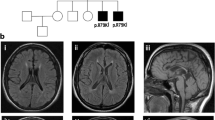

This boy is the first child of unaffected, non-consanguineous parents, a 27 year old mother and a 43 year old father. The family history is unremarkable in terms of neurological or metabolic diseases. Pregnancy was uncomplicated except vaginal bleedings in the first trimester. The boy was born at 41 weeks of pregnancy with unremarkable birth measurements (Table 1) and with two natal teeth (31 and 41). From the first day on feeding difficulties and truncal hypertonia were observed. At 6 months, global developmental delay and secondary microcephaly became evident: the boy was not able to bring his hands in the middle of his body, to grasp or to roll over. He had poor visual fixation. In addition, he showed motoric restlessness. Sleep was disturbed by sleep-onset and sleep-maintenance insomnia. Extensive work-up at the age of 6 months gave unremarkable results for basic blood and extended metabolic analyses. Brain MRI showed delayed myelination, signal alterations in brain stem and to a lesser extent in basal ganglia with restricted diffusion, hypoplastic corpus callosum and cortical—intense signals alterations close to the ventricles cranial (Fig. 2). Eye examination revealed pale papillae on both eyes. At re-evaluation at the age of 9 months, we saw a restless and severely retarded infant with truncal muscular hypotonia, hypertonia of the limbs, and repeated head banging and grimacing. He did not show social interaction with only short visual contact. Motor development was severely delayed, he could not grasp, roll over, or going in the 4-point quadruped position. Weight and length were unremarkable, but the OFC was microcephalic (− 2.8 SD). By the age of 2 years, he developed therapy-refractory seizures and melatonin-resistant sleep disturbances. Extended blood, urine, and CSF analyses all gave unremarkable results. Brain MRI confirmed the previous findings. In addition, suspicion of hypothalamic adhesion, asymmetry, and inhomogeneity of hippocampi were observed. MRI spectroscopy was inconspicuous. Eye examination confirmed optic nerve atrophy and strabismus, and revealed astigmatism and myopia. At the last clinical examination at the age of 3 years, he still had a poor head control, was non-ambulatory, non-verbal, and showed severe truncal hypotonia, poor social interaction, and medically refractory epilepsy. He had a poor weight gain, with a height of 83.5 cm (− 3.23 SD), weight of 10.4 kg (− 2.57 SD), and secondary microcephaly with OFC of 45.5 cm (− 3.9 SD).

MRI findings in individual 2 at 8 months of age. Myelination appears slightly delayed for age with arborisation of the frontal white matter not yet present. Increased T2 signal intensity of the decussation of superior cerebellar peduncle (black arrow head) and medial pallidi (black arrow) is noted. At the age of 5 months, these lesions had shown restricted water diffusion, suggestive of cytotoxic edema. The body of corpus callosum is hypoplastic (white arrow head) and bilateral subependymal heterotopias are noted at this level (open arrow head). In addition, hypothalamic adhesions are present (white arrow)